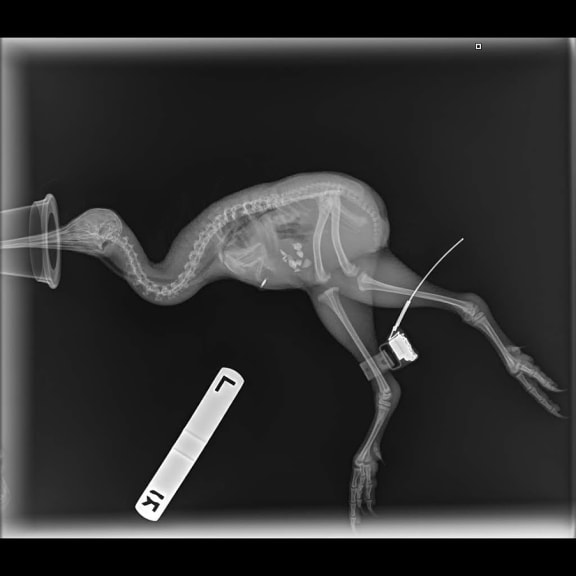

An x-ray of a Haast kiwi. Note the location transmitter attached to its leg. Photo: Wildlife Hospital Dunedin.